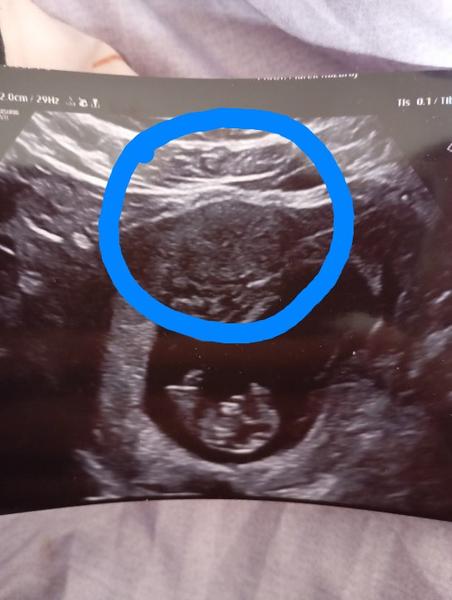

Je myom během těhotenství nebezpečný pro matku i dítě?

Celou dobu tam nic neviděli, az najednou teď nechápu. Minulý týden jsem taky byla na utz a nic